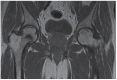

Avascular necrosis (AVN) of the femoral head is caused by disruption of the blood supply to the proximal femur. The alterations in the blood supply may occur following a traumatic event or result from a non-traumatic cause. Femoral neck fracture and hip dislocation and associated surgical procedures, corticosteroid therapy, and alcohol abuse frequently lead to AVN development. Type of fracture (displaced or undisplaced) and time between injury and surgery are the most critical factors in assessing the risk of developing AVN. Diagnosis of AVN can be established based on patients' complaints, medical history, and radiographic findings. There is no consensus on the treatment of patients with AVN to date. Non-surgical methods are dedicated to patients in the early pre-collapse stages of the disease and consist of pharmacotherapy and physiotherapy. Surgery is recommended for patients with advanced disease.